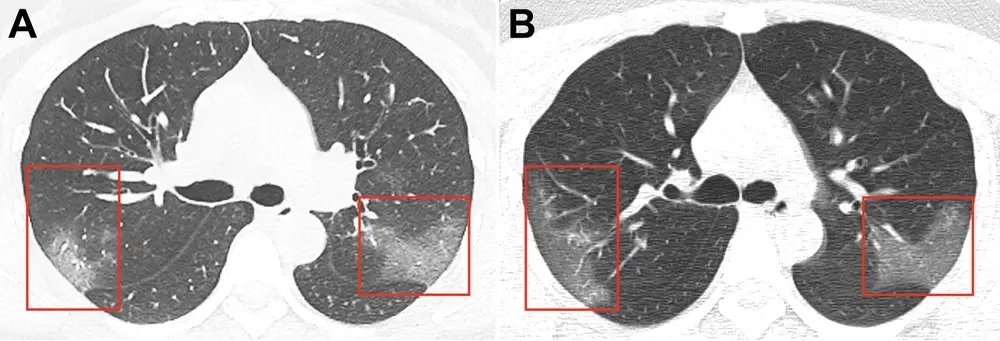

Vài bệnh nhân thở hổn hển khi họ chỉ đi bộ, theo South China Morning Post. Ảnh chụp cắt lớp phổ của 9 bệnh nhân cho thấy dấu hiệu tổn thương.

phuc hoi sau nhiem Covid-19 anh 3

Ảnh chụp CT phổi của bệnh nhân Covid-19. Các mảng trắng mờ cho thấy phổi đầy dịch. Ảnh: Business Insider.